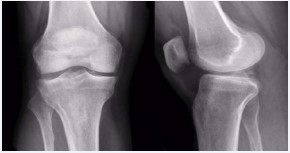

A 44 year old patient, male suffering from rheumatoid arthritis, complaining pain and clamping of the right knee for 5 years during the daily routine activities, with no associated trauma. The patient presents with a history of physiotherapy treatment and two arthroscopic procedures, with no improvement of symptoms. Radiographic examination revealed an image consistent with an intra-articular loose body in the medial compartment, in the topography of the posterior horn of the meniscus (Figure 1). The Magnetic Resonance Imaging (MRI) enabled the identification of bone tissue internal to the posterior horn of the medial meniscus (Figure 2). The surgical treatment was performed by arthroscopy via inter condylar access through the anterolateral and anteromedial portals (Figure 3) to position the optics and visualization of the posterior compartment (Figure 4). We identified the mensicalossicle adjacent to the posterior horn of the medial meniscus (Figure 5) and performed its removal utilizing basket forceps associated with economic resection of the posterior horn of the meniscus, due to the intimate anatomic relation between the two structures (Figures 6,7). The material was subjected to histopathological analysis, which identified fragments of meniscus containing hyaline alterations and metaplastic ossification, apart from a degenerative process, fibrosis, and foci of neovascularization (Figure 8). The patient evolved satisfactorily, with complete recovery of the range of motion and absence of joint locking symptoms, being that his last clinical evaluation was done with 3 months of postoperative. The last X-ray showed the absence of the bone body on the posterior compartment of the knee (Figure 9).

Figure 1: x-rays of the knee showing the bone body in the posterior region of the medial compartment.